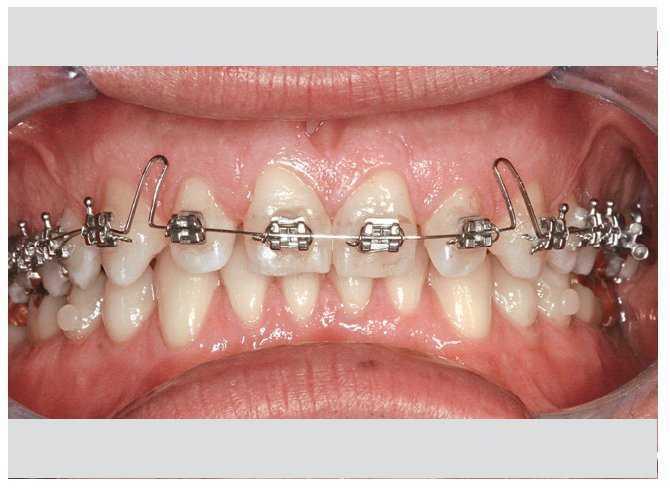

El uso de arcos de níquel-titanio superelásticos en combinación con brackets de técnica bidimensional en el maxilar permitió conseguir la máxima expansión y protrusión sin conflictos con los brackets colocados en la mandíbula (fig. 7). En poco tiempo se corrigió la mordida cruzada y se pudo concluir la armonización y la coordinación de las arcadas (figs. 8 a 10). Las mejoras estéticas y dentales son más que evidentes (figs. 11 y 12). El tratamiento activo finalizó con la retirada de la aparatología multibandas y a continuación se colocaron los dispositivos de retención correspondientes (figs. 13 y 14).

Figura 7. Se consigue la corrección sin contratiempos.

Figura 8. Corrección de la mordida cruzada.